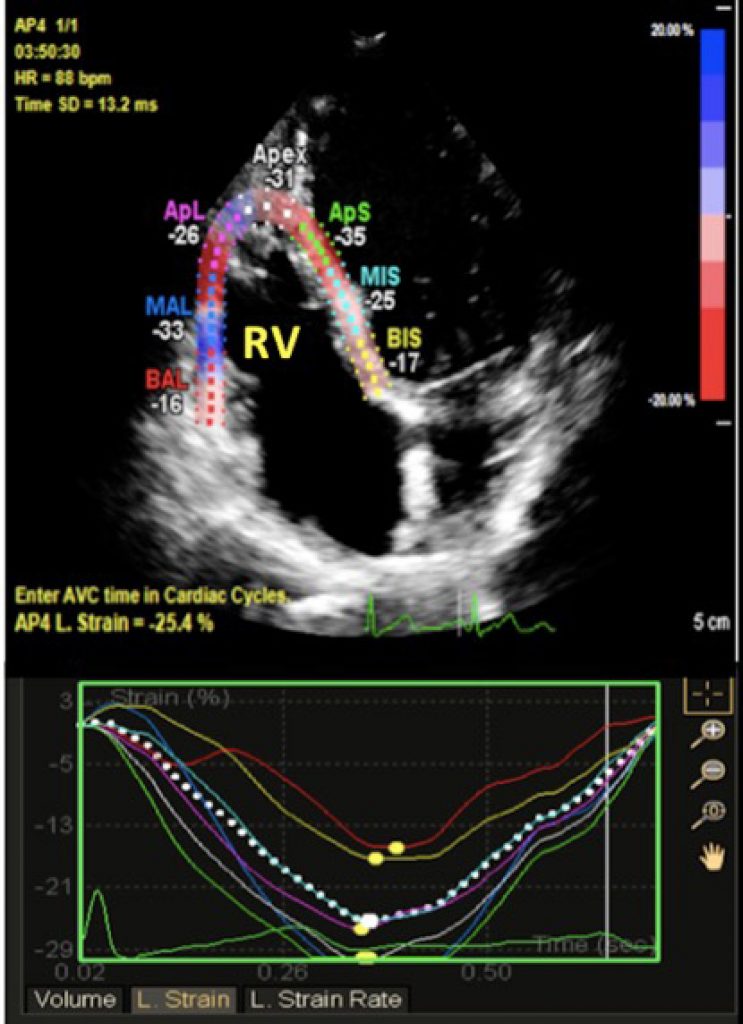

The aim of this study was to evaluate the magnitude of RV dysfunction by means of speckle tracking echocardiography (STE) in patients with chronic obstructive pulmonary disease (COPD) and to investigate whether STE could be used as an index of RV improvement after a pulmonary rehabilitation (PR) program.

Forty-six patients with COPD undergoing PR program and 32 age-sex matched healthy subjects were enrolled. RV function was evaluated at admission and after PR program by conventional two-dimensional echocardiography (2DE) and STE. In addition, exercise tolerance of subjects was evaluated using the six-minute walk test (6MWT).

COPD patients had worse RV function according to STE and 2DE as well. STE was more sensitive than conventional 2DE in determining RV improvement after PR program – RV global longitudinal strain (LS): 20.4 ± 2.4% vs. 21.9 ± 2.9% p < 0.001 and RV free wall LS: 18.1 ± 3.4% vs. 22.9 ± 3.7%, p < 0.001). RV free wall LS was directly related to distance walked at baseline 6MWT (r = 0.58, p < 0.001) and to the change in the 6MWT distance (6MWTD ∆) (r = 0.41, p = 0.04).